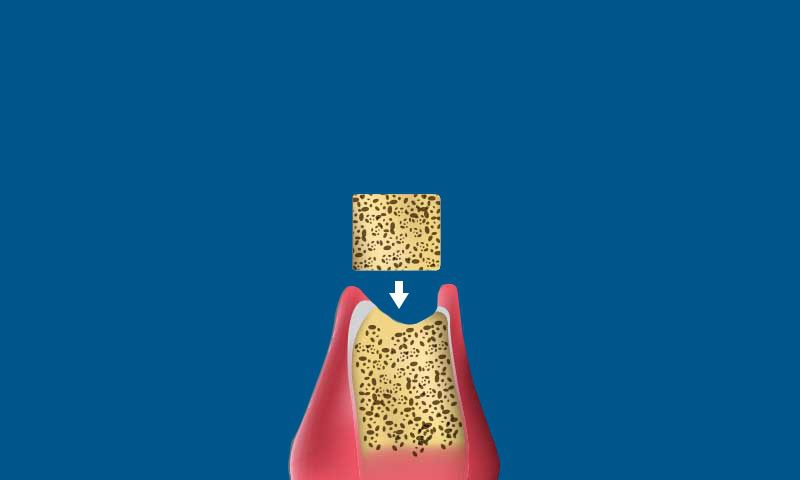

Bone Grafting. If your jawbone lacks the mass needed to accept an implant, we place a bone graft to strengthen the area. It may require several months of healing before we place the dental implant.